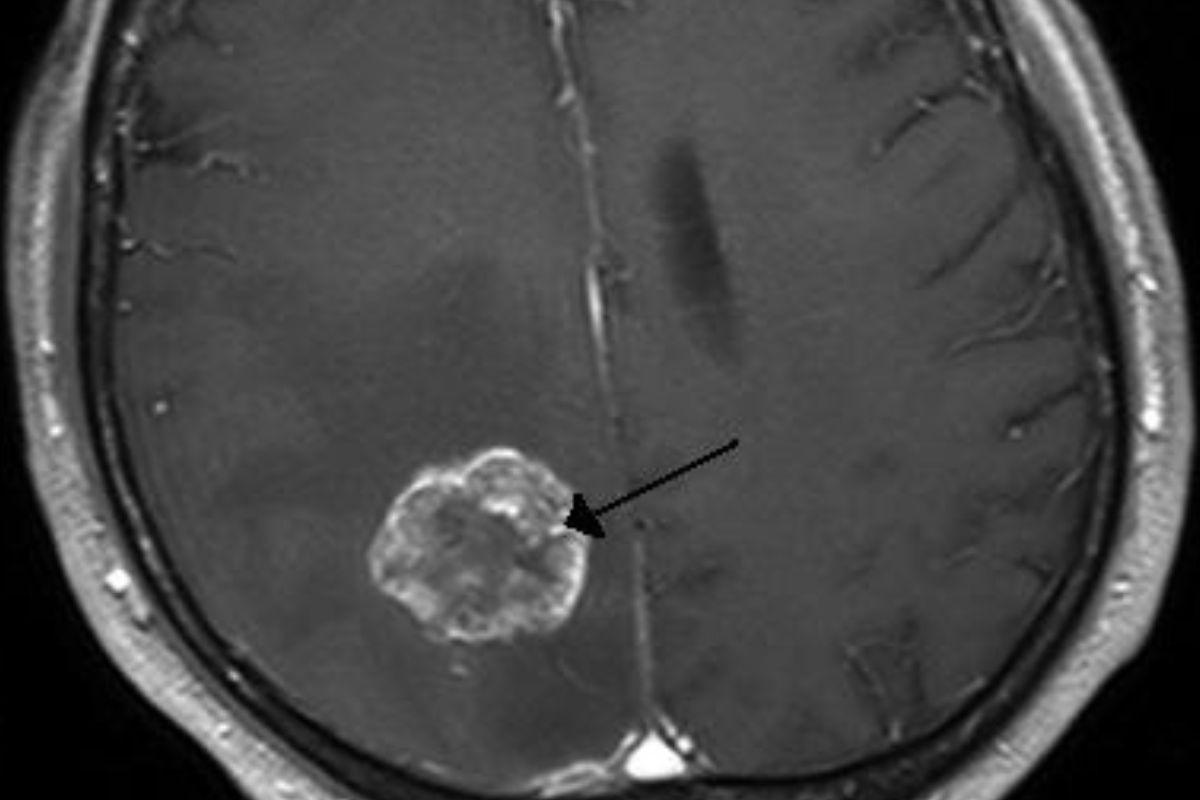

Na manhã que se iniciou, as dores pioraram e Kane chegou a ter convulsões, o que fez com que os médicos fizessem um exame de ressonância magnética, chegando a um resultado que foi divulgado aos pais do garoto: “Steve e eu fomos levados para uma sala e nós disseram que haviam descoberto um quadro de hidrocefalia aguda, que é um acúmulo de pressão no cérebro pelo excesso de líquido. Isso não foi o pior de tudo, no entanto. Eles também encontraram um grande tumor” relatou a mãe.

Sendo levado para uma cirurgia de emergência para tratar a hidrocefalia, Kane voltou dois dias depois para a remoção do tumor, uma cirurgia bem sucedida que levou aproximadamente oito horas, também trazendo mais uma informação, o tumor era benigno. O adolescente recebeu alta quatro dias depois, mas precisará voltar ao hospital devido à outra operação que deverá ser feita após a volta da hidrocefalia.